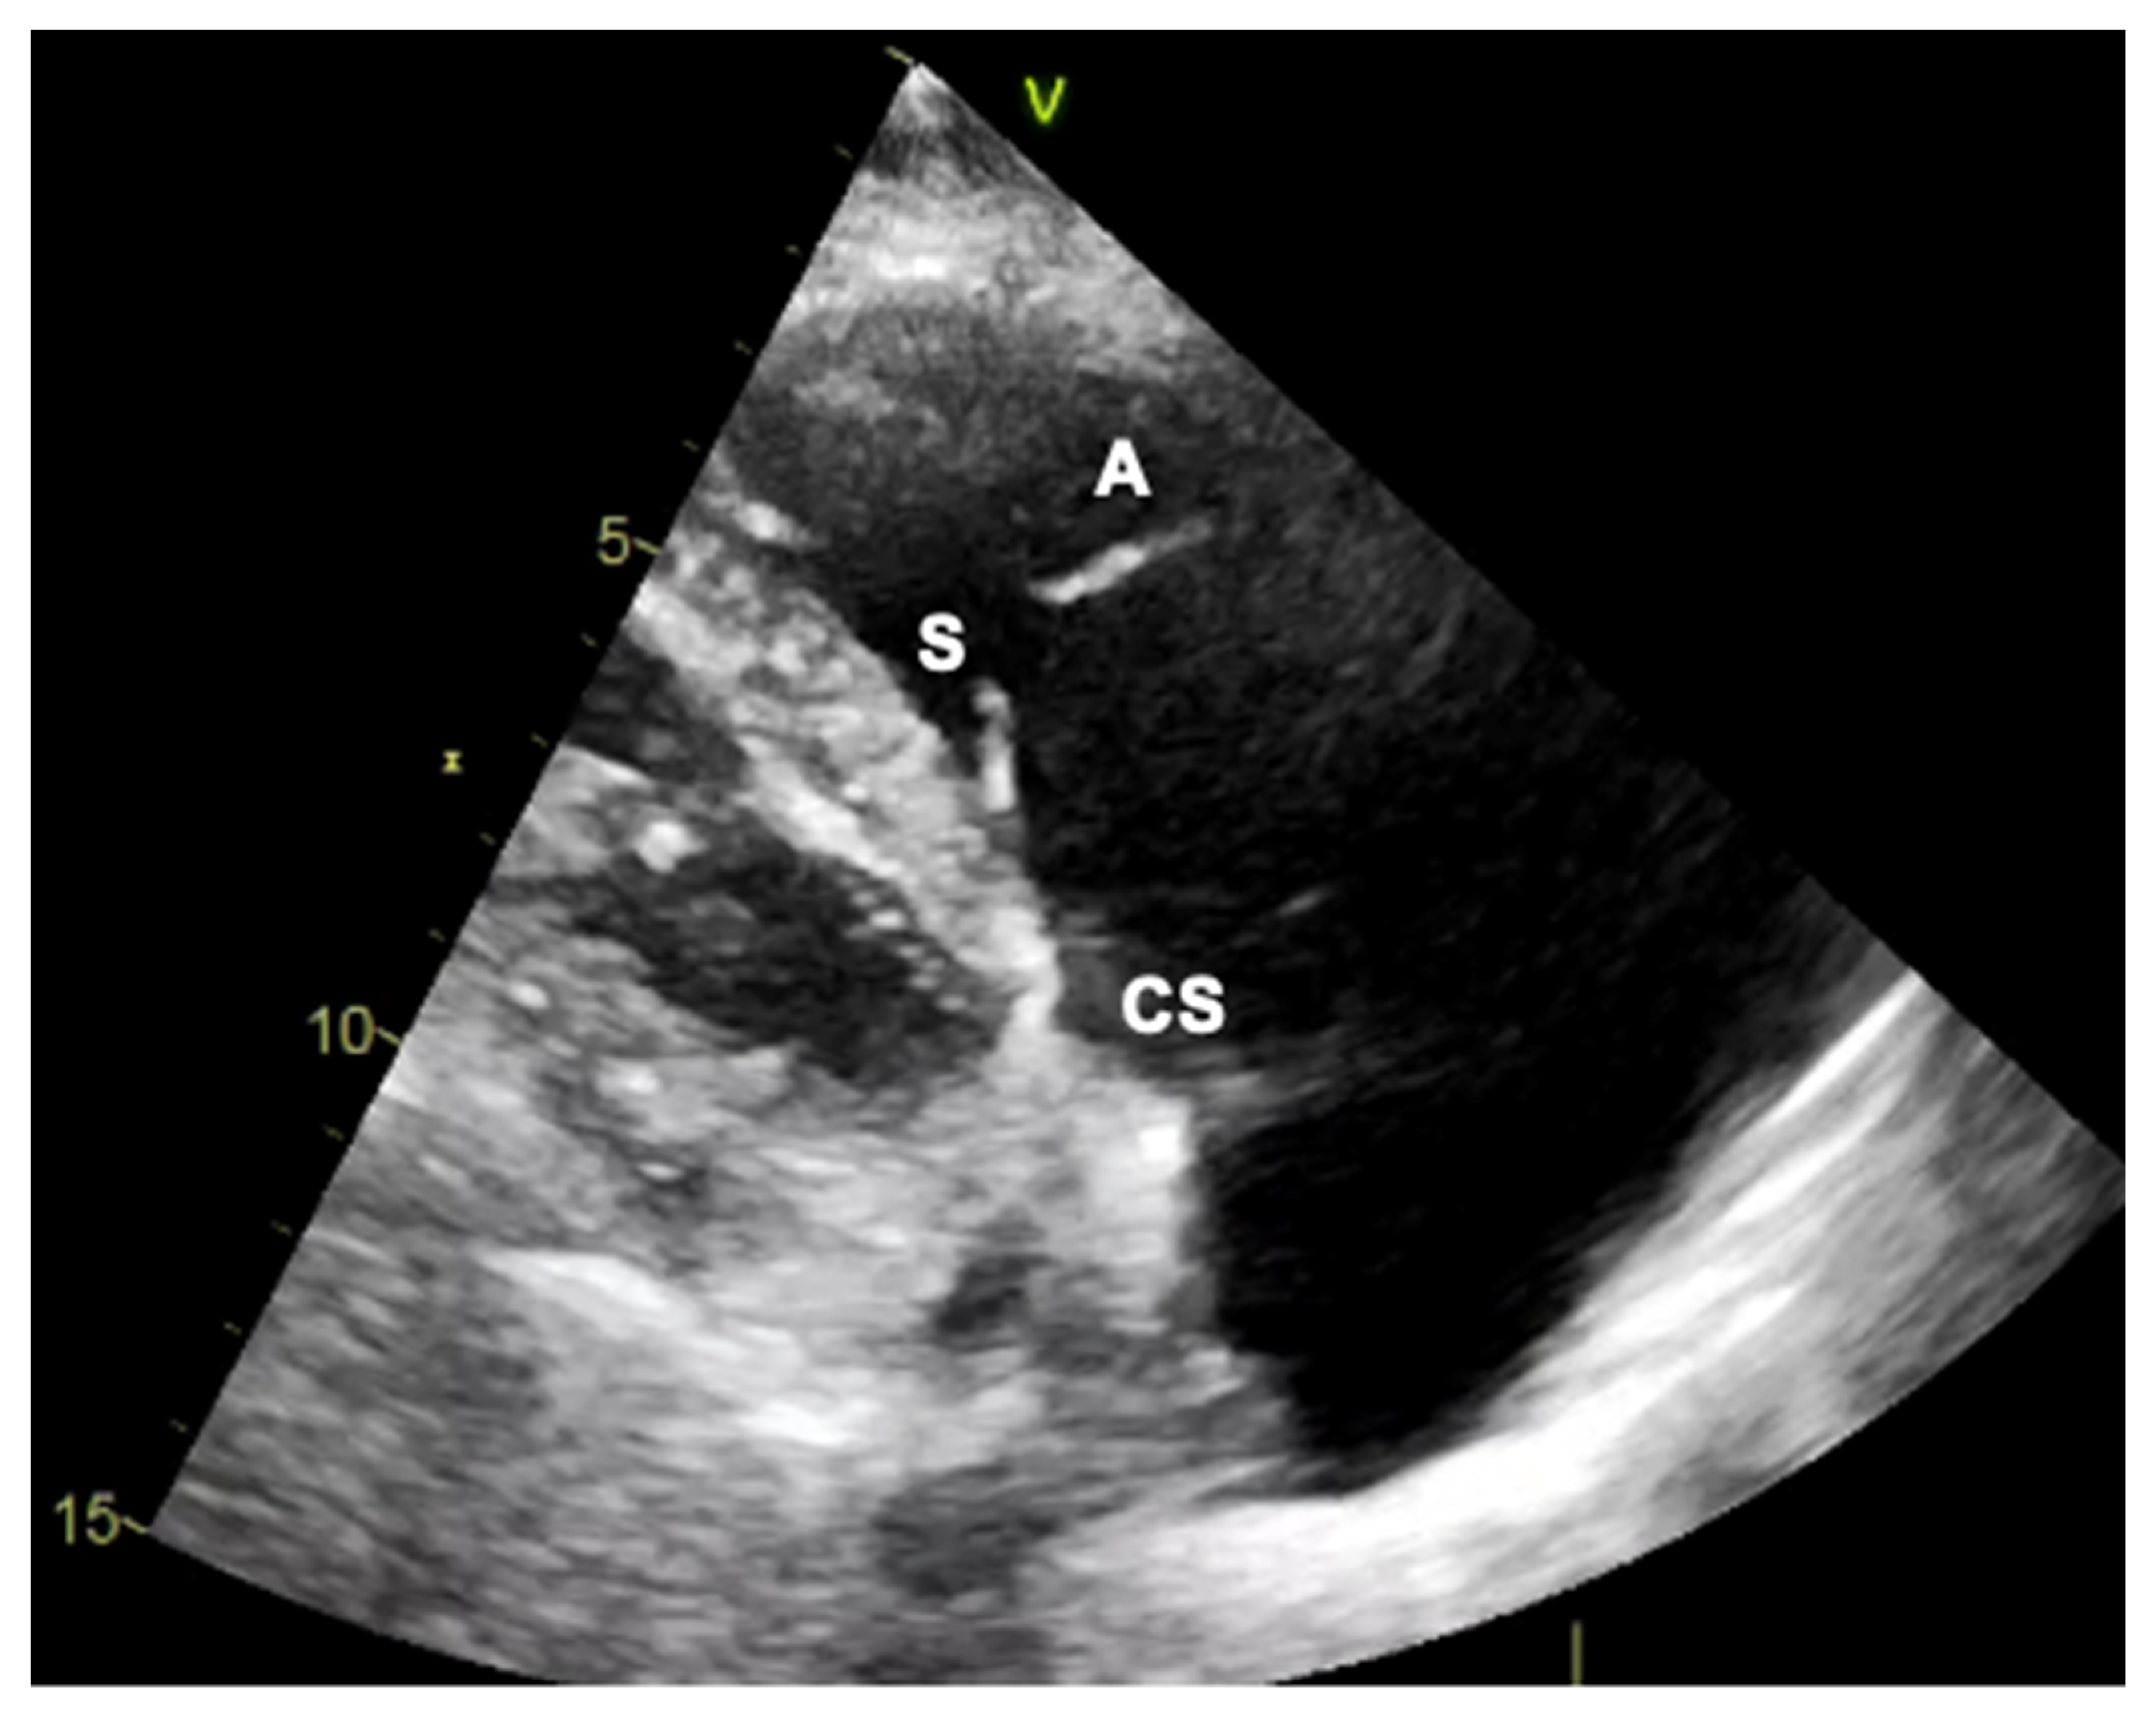

2.1. Two-Dimensional and Three-Dimensional Transthoracic and Transesophageal Echocardiography

3.1. Two-Dimensional and Three-Dimensional Transesophageal Echocardiography

- Ancona, F.; Stella, S.; Taramasso, M.; Marini, C.; Latib, A.; Denti, P.; Grigioni, F.; Enriquez-Sarano, M.; Alfieri, O.; Colombo, A.; et al. Multimodality imaging of the tricuspid valve with implication for percutaneous repair approaches. Heart 2017, 103, 1073–1081. [Google Scholar] [CrossRef] [PubMed]

- Agricola, E.; Ancona, F.; Stella, S.; Rosa, I.; Marini, C.; Spartera, M.; Denti, P.; Margonato, A.; Hahn, R.T.; Alfieri, O.; et al. Use of Echocardiography for Guiding Percutaneous Tricuspid Valve Procedures. JACC Cardiovasc. Imaging 2017, 10, 1194–1198. [Google Scholar] [CrossRef]